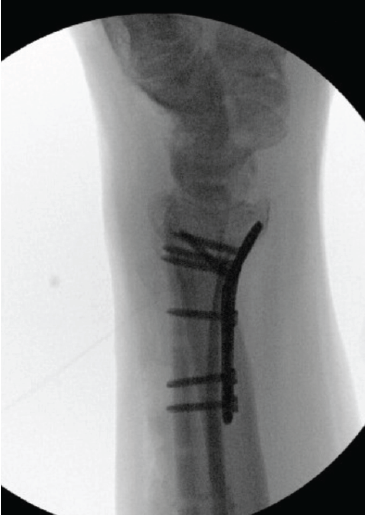

Fixation of 3-Part Intra Articular Distal Radius Fracture with Combined Volar Plate and Dorsal Spanning Plate: A Case Report

Anderson Lee , Brian Rao , Dave Yatsonsky , Kyle Behrens , Phillip J. Stokey , Nabil Ebraheim